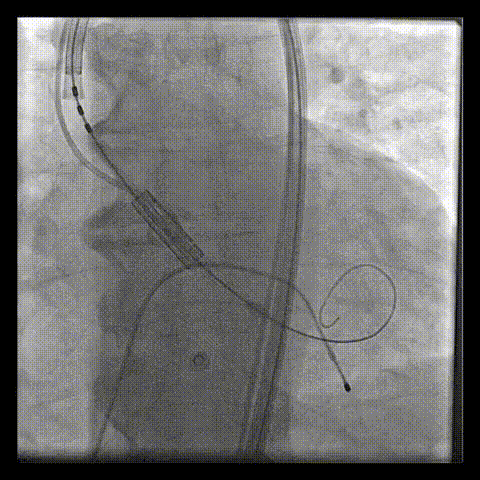

آنژیوپلاستی با رسوب شدید کلسیم در عروقتوسط دکتر عارف فاتحی فوق تخصص آنژیوگرافی و آنژیوپلاستی(قلب